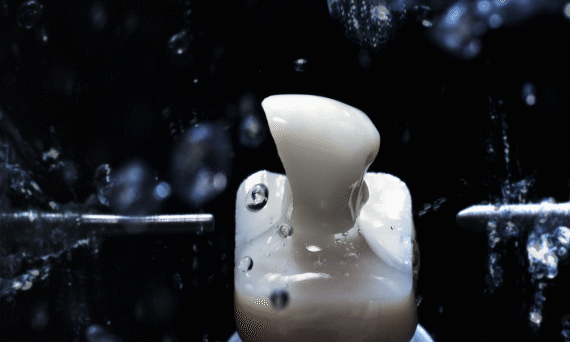

传统制作牙冠需要取模、切削、烧结、上瓷、上釉等8个步骤,一个环节错误就会导致数据失准,出现误差,现在通过数字化CAD/CAM设备,精确到微米,制作假牙的时间可以提速到2小时,就能完成最终戴牙,修复效率大大提高。

通过德国CAD/CAM中心的数字化设备,为患者完成个性化基台和临时牙冠的制作。经过高科技仪器的精密打磨与切削,与患者缺牙位吻合的牙体即在术前整备完好,等待着填充患者缺牙位置,实现即刻负重。

全套德国数字化极简种植真正做到术前种植方案可预见,种植效果可预知,种植牙体可预成。